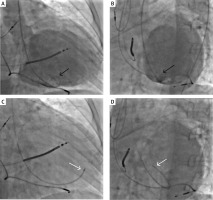

Figure 1

An example of an intracardiac, trans-catheter, needle-based, cardiopoetic stem-cell delivery procedure. A, B – Ventriculography (A – antero-posterior (AP) and B – left anterior oblique (LAO) view) prior to trans-endocardial cell delivery; black arrows indicate the tip of pigtail catheter; C, D – injection catheter attached to the target cardiac wall in the corresponding projection (C – AP, D – LAO view); white arrows indicate the tip of a needle-tipped catheter for cell delivery